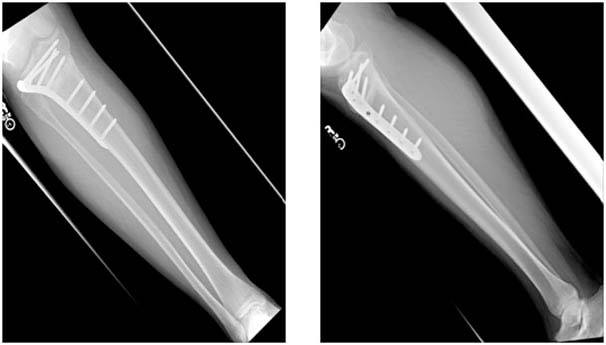

4.Postoperative images showing the use of a titanium plate and a synthetic graft to achieve the desired correction.